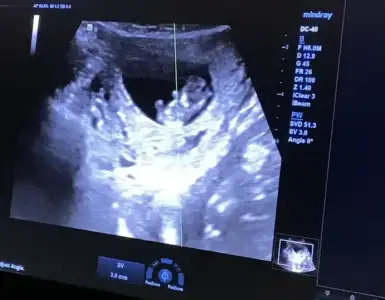

9+2 günlük hamileyim. Kasım ayının ilk haftası görünüyor doğum ama sürpriz yapıp Ekim ayında da gelebilir.

Bugün kontrolüm vardı, Elhamdülillah her şey yolunda gidiyor.

Belki içinizde cinsiyet tahmini yapabilen olur diye ultrason görüntüsünü paylaşmak bu vesile ile de tanış olmak istedim